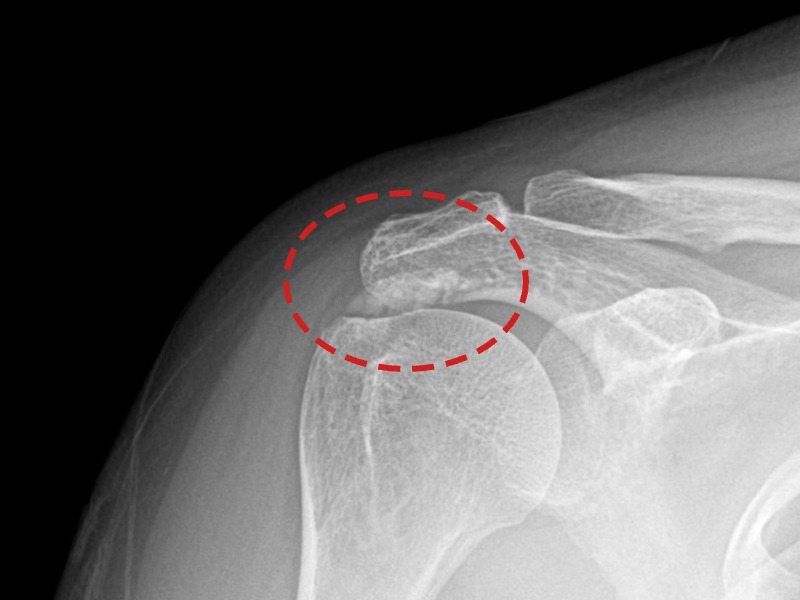

[촬영시기:21.10.21~21.10.30]

[석회분쇄흡입술] 우측 어깨 통증과 운동 제한으로 일상생활이 불편해진 30대 여성 환자로, X-ray에서 우측 극상근건 내 석회 침착이 확인되어 석회분쇄흡입술을 시행하였습니다.